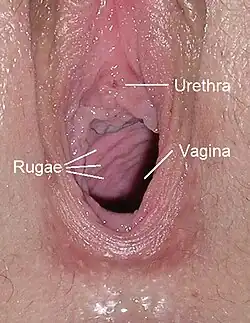

Die hintere Vaginawand (Paries posterior vaginae) ist durch die Lage des Uterus etwas länger als die vordere Vaginawand (Paries anterior vaginae).[6] Im ungedehnten Zustand ist sie durch das Parakolpium abgeflacht, die vordere und die hintere Wand berühren sich, sie werden von den Nachbarorganen komprimiert, und umschließen das Lumen der Vagina, das einen H-förmigen Spalt bildet und dadurch eine Entfaltung ermöglicht, ohne große Spannung zu erzeugen.[7] Die Hinterwand (Dorsalwand) der Vagina ist durch Bindegewebe (Septum rectovaginale) mit dem Mastdarm und die Vorderwand über das Septum vesicovaginale und das Septum urethrovaginale mit der Harnblase und der Harnröhre verbunden.[2] An der vorderen und hinteren Vaginawand befinden sich zudem Querfalten, die als Scheidenrunzeln (Rugae vaginales) bezeichnet werden und eine vordere und eine hintere Runzelsäule bilden (Columnae rugarum anterior et posterior). Diese verstärken beim Geschlechtsverkehr die Reizwirkung und stellen zugleich eine Dehnungsreserve für die Geburt dar.[8]

Die Vagina mündet mit ihrer Öffnung (Ostium vaginae oder Introitus vaginae) in den Scheidenvorhof der Vulva. An der Vaginalöffnung gibt es eine Ansammlung von Schleimhautfalten, meist in Form eines Kranzes (vaginale Corona), die als Hymen bezeichnet werden.[9]

Blick in das vordere Drittel der Vagina, mit typischen Querfalten (Rugae vaginales); oberhalb die Harnröhrenmündung (Carina urethralis vaginae)

Blick in das vordere Drittel der Vagina, mit typischen Querfalten (Rugae vaginales); oberhalb die Harnröhrenmündung (Carina urethralis vaginae)